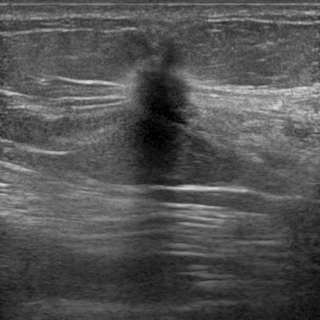

超音波検査は高濃度乳房の検査やマンモグラフィーができないときにも威力を発揮する検査で、検査の時の病変の場所の確認にも用います。

図3 超音波検査